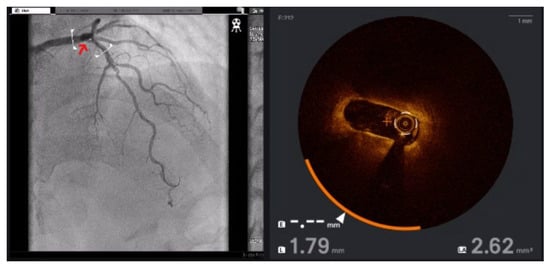

To address these challenges, adjunctive imaging modalities have been adapted to enable ultra-low contrast PCI. Intravascular ultrasound (IVUS) provides detailed cross-sectional images without reliance on contrast media (Figure 1) and is recommended in complex interventions [5,6]. OCT provides high-resolution plaque characterisation and stent assessment (Figure 2), but requires flushing, typically with contrast media; however, substitutes such as low-molecular-weight dextran and heparinised saline have shown promise as alternatives [51,52,53,54]. DCR software overlays a live coronary roadmap onto the fluoroscopic image, enabling navigation of coronary tools and stent delivery without repeated contrast injections (Figure 3) [7,55]. While these modalities provide valuable anatomical information, they remain dependent on fluoroscopic platforms and do not eliminate contrast use entirely, highlighting the potential role for complementary navigation technologies such as EAMS.

Figure 3. JL 3.5 coronary catheter (arrow) positioned in the left coronary cusp in LAO cranial view following coronary angiography (left). DCR map visualising the coronary tree without contrast injection (right).